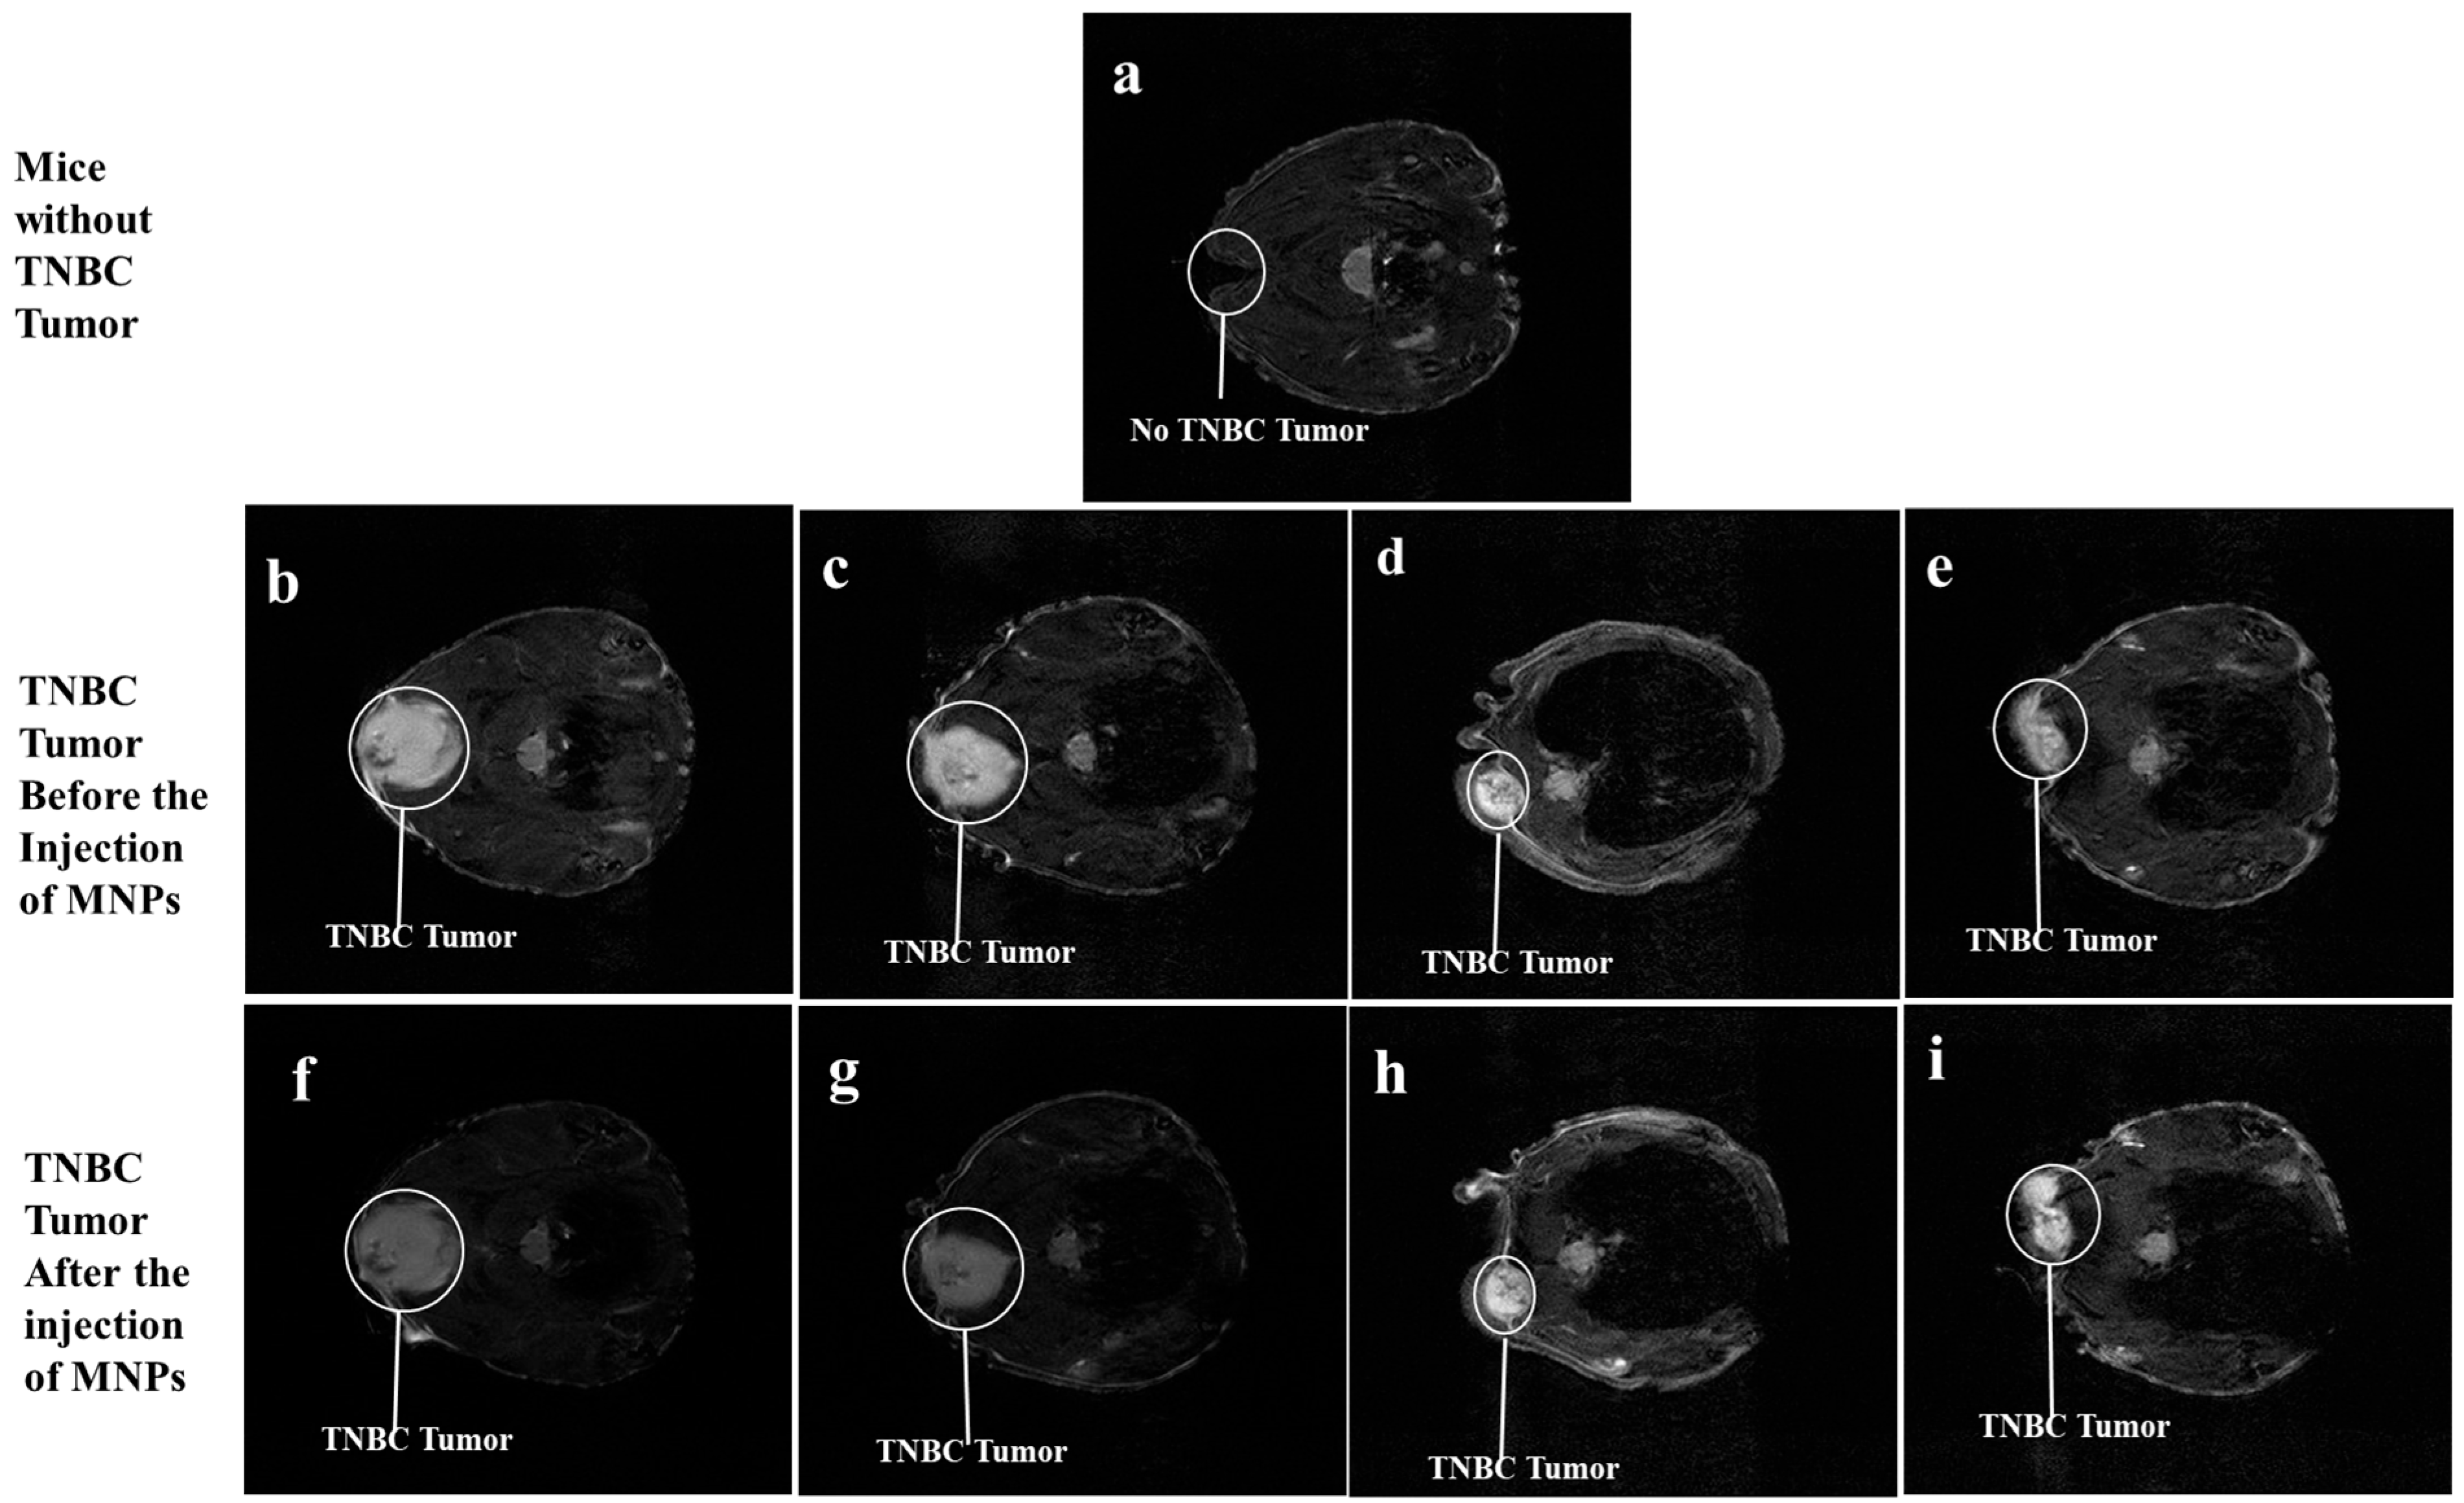

3.4. T2-Weighted Magnetic Resonance Imaging

Figure 4a is the dorsal view of mice without any induced tumors. Figure 4b–i show representative images of the sectional dorsal views of mice induced with TNBC tumors on their trunks, with the TNBC tumor appearing as a gray-colored irregular mass encircled in white. Figure 4b–e show the T2-weighted MRI scans of the TNBC tumor before the injection of MNPs, while the images in Figure 4f–i reveal the T2-weighted 3T MRI scans of the TNBC tumor tissue 2 h after the injection of the MNPs in the nude mice via the tail vein. The T2-weighted 3T MRI scans in Figure 4f and Figure 4g appear darker, 2 h post-injection of BMNR and LCMNR, respectively. The T2-weighted MRI scans in Figure 4h and Figure 4i show images taken 2 h after injection of BSSMNP and LCSSMNP, respectively.

Figure 4. T2-weighted 3 Tesla MRI scans. (a) is the 3T MRI scans of mice before TNBC tumor induction. (be) are the 3 Tesla MRI scans of the TNBC tumor induced in nude mice. (f) is a 3 Tesla MRI scan of the TNBC tumor shown in (b), 2 h after the mice were injected with BMNR. (g) is a 3 Tesla MRI scan of the TNBC tumor shown in (c), 2 h after the mice were injected with LCMNR. (h) is a 3 Tesla MRI scan of the TNBC tumor shown in (d), 2 h after the mice were injected with BSSMNP. (i) is a 3 Tesla MRI scan of the TNBC tumor shown in (e), 2 h after the mice were injected with LCSSMNP.